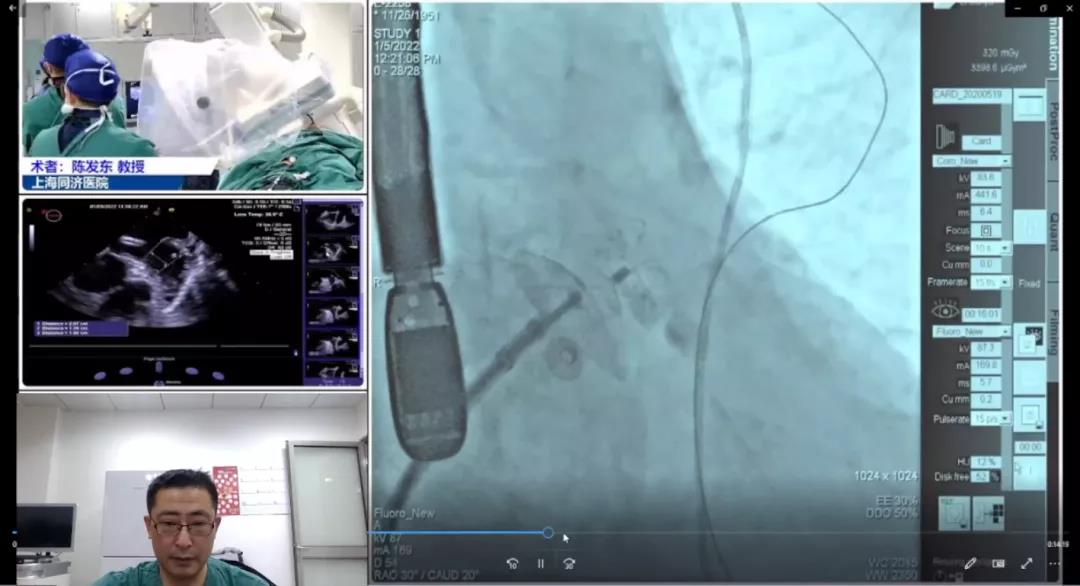

上海市同济医院陈发东教授团队

患者男性,70岁,患有持续性房颤、心尖肥厚性心肌病及高血压,拟行房颤消融+左心耳封堵“一站式”手术。患者于全麻状态下行右股静脉及房间隔穿刺,建立右心房至左心房通路,在猪尾保护下行心耳造影,测量左心耳锚定区约为15mm,封堵区约为23mm,结合造影和测量结果综合考虑,选用LAmbre™2032封堵器进行封堵,多角度造影及TEE显示封堵效果理想,无残余分流,牵拉测试十分稳定,符合COST原则,手术取得圆满成功。